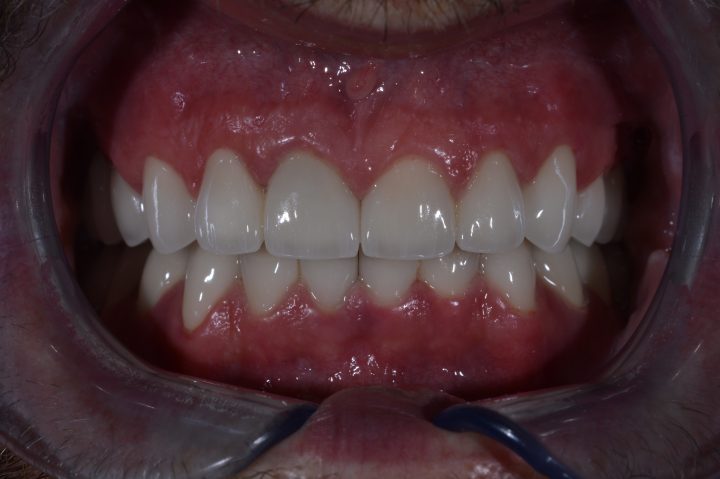

In der gleichen Behandlung hat er noch oben 4, und unten 6 Implantate bekommen, daneben hat er im Ablauf den 5 Tagen provisorischen Zahnersatz gekriegt.

Danach hatte er 4 Monate lange Heilungszeit, bald war den endgültigen Zahnersatz fertig: Oben wird eine Stegprothese auf 4 Implantate bearbeitet, unten wird eine Brücke auf 6 Implantate befestigt.

Chris Leben hat sich radikal nach der Behandlung verändert. Er wagt wieder kennenlernen und lebt schon zwanglos.